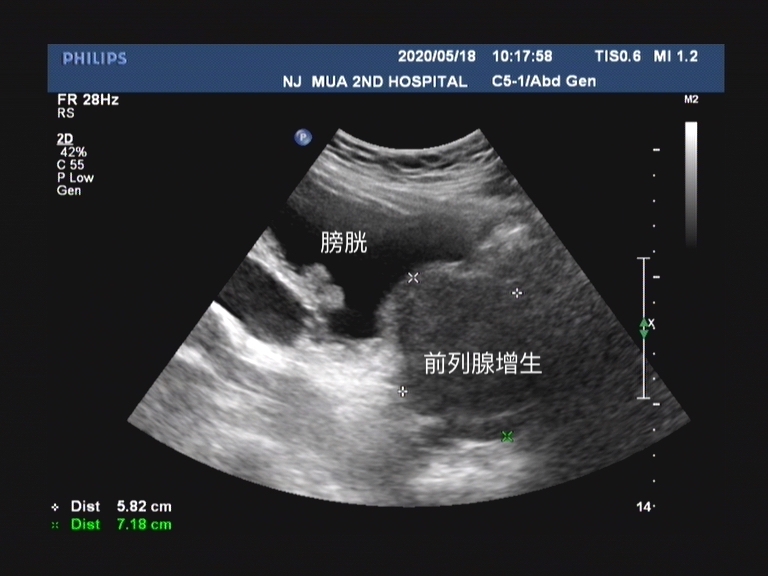

是指急性发生的无法排尿,导致尿液滞留于膀胱内的一种症候群,常伴随由于膀胱内尿液胀满而引起的明显尿意、疼痛和焦虑等症状。

急性尿潴留多发生于男性,有统计显示65%的急性尿潴留是由于前列腺增生影响的。那为什么在冬季尤其是在冬季夜间,前列腺增生的患者出现急性尿潴留的概率会明显增加呢?

前列腺增生的临床症状分为储尿期症状和排尿期症状,如果感兴趣的可以看下我之前的文章。那在出现急性尿潴留的情况时,是老年人的排尿出现了问题,也就是前列腺增生的排尿期症状加重。

尿道是从前列腺内穿过,前列腺的充血水肿会压迫尿道,导致尿路梗阻

每逢冬季,因为天气寒冷,老年人活动减少,体表血管收缩,因而血液循环减慢,加重了前列腺的充血,充血会导致前列腺肿大,这个时候就会导致前列腺增生症状明显加重。又由于冬季,很多老年人喜欢饮酒或者说泡澡,前列腺充血更为明显,堵塞尿道,更容易导致出现小便不能排出的情况。